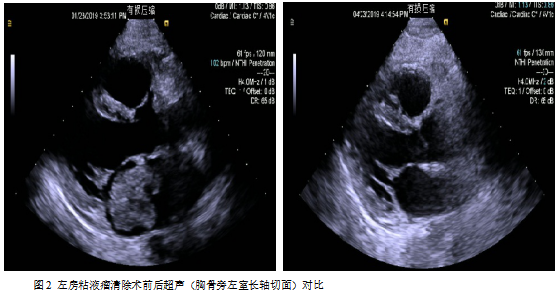

手术:目前左房粘液瘤患者手术指征粘液瘤可阻塞瓣膜开口导致心力衰竭或心跳骤停,瘤栓脱落导致脑检塞等也可以引起死亡。因此,一且确诊,立即争取手术治疗。一般心脏患者如有长期发热、心力衰竭、贫血、血沉增快等现象,须延缓手术。但对心脏粘液瘤患者需具体分析,否则可能丧失手术机会。如有高热、血沉快,全身症状为主要表现,并且考虑是由粘液瘤引起,应立即手术,摘除肿瘤能使体温下降、心率变慢、血沉恢复正常、心衰得到控制。如果感染性心内膜炎引起的高热、心力衰過,不宜急于手术,应该控制高热、心衰后手术,以免发生严重的并发症[1-2]。该患者左房占位病变巨大,且血流动力学不稳定,肿物随左心室舒张通过二尖瓣从左房脱入左室,左心室收缩又返流回左房,因粘液瘤部分阻塞二尖瓣口,随体位变化有间歇性昏厥的患者,我们选择严格限制卧床体息,应用静脉滴注多巴胺强心维持血压,同时给予利尿药减轻肺水肿,准备急症手术。

术后病理:(左心房肿瘤)肿瘤细胞呈圆形、梭形及星芒状,单个散在或呈条索状排列,其周可见空晕,间质富于粘液,部分肿瘤细胞围绕血管周围排列,血管扩张充血伴大片出血。形态符合粘液瘤。